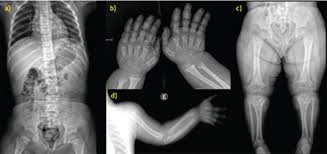

Achondroplasia